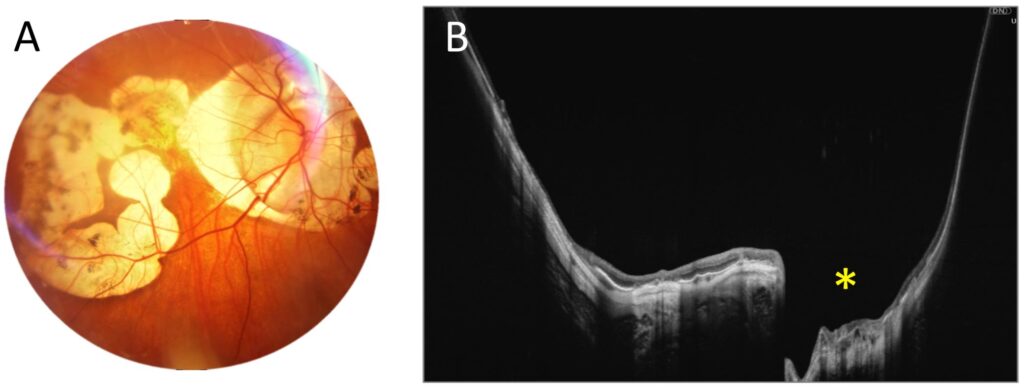

Another figure (Figure 3) demonstrates posterior staphyloma due to high myopia, which extends both vertically and horizontally over a significant area. With a full-range UWF scan that is 22 mm wide and 6 mm high, we can trace the significant depression in the central part of the retina (asterisk) and the strongly curved shape of the posterior pole.

Figure 3. Posterior staphyloma due to high myopia (male, age 43). (A). Colour fundus photograph showing extensive atrophy. (B). A 22 mm wide UWF full-range OCT scan of the posterior pole. The asterisk indicates a localized outpouching around the optic disc.